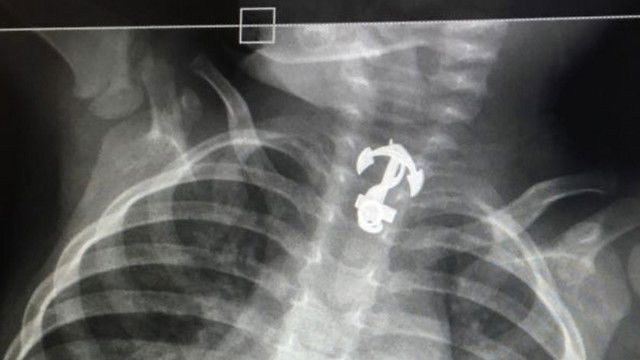

מקרה נדיר ונס של ממש אירע לילד בן שנתיים תושב אשדוד שהגיע עם הוריו לקופת החולים מכבי לאחר חשש לדלקת ריאות. טכנאית הרנגטן שביצעה את הבדיקה לילד הופתעה לגלות בוושט גוף זר גדול ממתכת בצורת עוגן.

כשראתה את תוצאות הצילום, פנתה הטכנאית אל ההורים. "סיימתי לצלם, ניגשתי למחשב לראות את הצילום, ראיתי את העוגן הזה בצילום ומיד שאלתי את האימא אם לילד יש תליון, שרשרת, למרות שראיתי שלילד אין כלום והוא היה ערום לגמרי בזמן הצילום", משחזרת גבאי. "שאלתי את האימא אם היא מכירה דבר כזה, אולי זה המחזיק של המוצץ? אבל האם לא הכירה. ביקשתי ממנה שנעשה צילום נוסף כדי לוודא שזה אכן בתוך הגוף, ולאחר הצילום הנוסף שהבנו שהילד אכן בלע חפץ זר".

בבית החולים אסותא טופל הילד על ידי מנהלת חדר המיון ד"ר הגר סופרמן וסגן מנהל מחלקת אף אוזן גרון, ד"ר טל מרום. הוא הוכנס בבהילות לצילום חזה, ותוך זמן קצר ולאחר בדיקות נוספות, הועבר לחדר הניתוח. במהלך הניתוח הוחדר לו צינור אופטי לוושט, על מנת לשלוף את הגוף הזר - והעוגן יצא בשלמותו. לאחר הניתוח אושפז הילד במחלקת כירורגית לילדים וביום שישי הוא שוחרר לביתו.